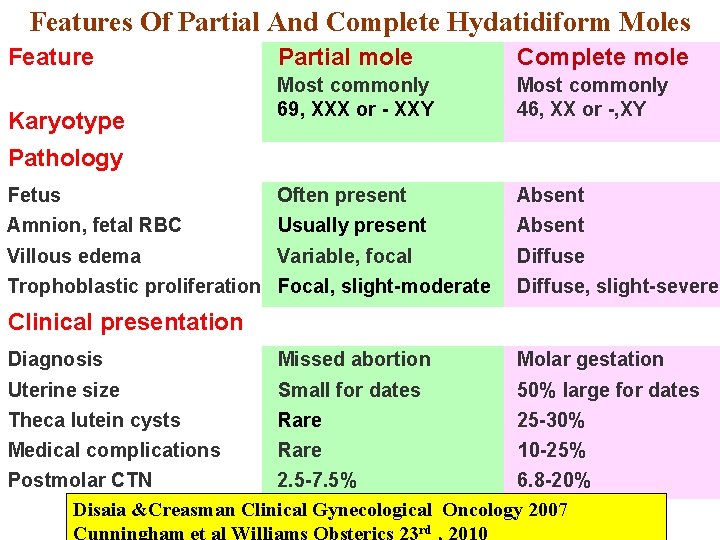

Features Of Partial And Complete Hydatidiform Moles Feature Partial mole Complete mole Most commonly 69, XXX or - XXY Most commonly 46, XX or -, XY Fetus Often present Absent Amnion, fetal RBC Usually present Absent Villous edema Variable, focal Diffuse Karyotype Pathology Trophoblastic proliferation Focal, slight-moderate Diffuse, slight-severe Clinical presentation Diagnosis Missed abortion Molar gestation Uterine size Small for dates 50% large for dates Theca lutein cysts Rare 25 -30% Medical complications Rare 10 -25% Postmolar CTN 2. 5 -7. 5% 6. 8 -20% Disaia &Creasman Clinical Gynecological Oncology 2007 rd